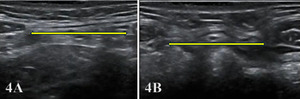

Figure 1A: Transducer Placement for Rectus Abdominis in Long Axis (LAX)

To obtain a LAX view of a rectus belly, place a high-frequency linear transducer parallel to the muscle fibers, centered ~2–3 cm lateral to the LA at the level of interest (e.g., 2 cm above the umbilicus). The transducer marker faces cranially. Slide cranio-caudally to visualize tendinous intersections and the anterior/posterior rectus sheaths (note posterior sheath disappears below the arcuate line). Optimize depth so the posterior border of RA sits in the lower third of the image; set focal zone at or just deep to the posterior sheath.

Figure 1B: Transducer Placement for Rectus Abdominis in Short Axis (SAX)

To obtain a SAX view, rotate the transducer 90° with the marker toward the patient’s right and center over the LA at the chosen level (−2/0/+2 cm relative to the umbilicus). Identify the echogenic linea alba midline, paired RA bellies on either side, and their sheaths.